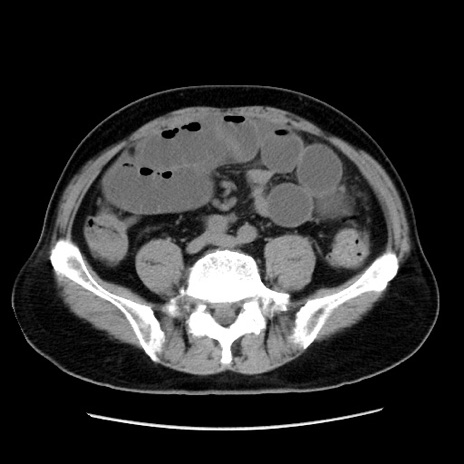

冠状断像